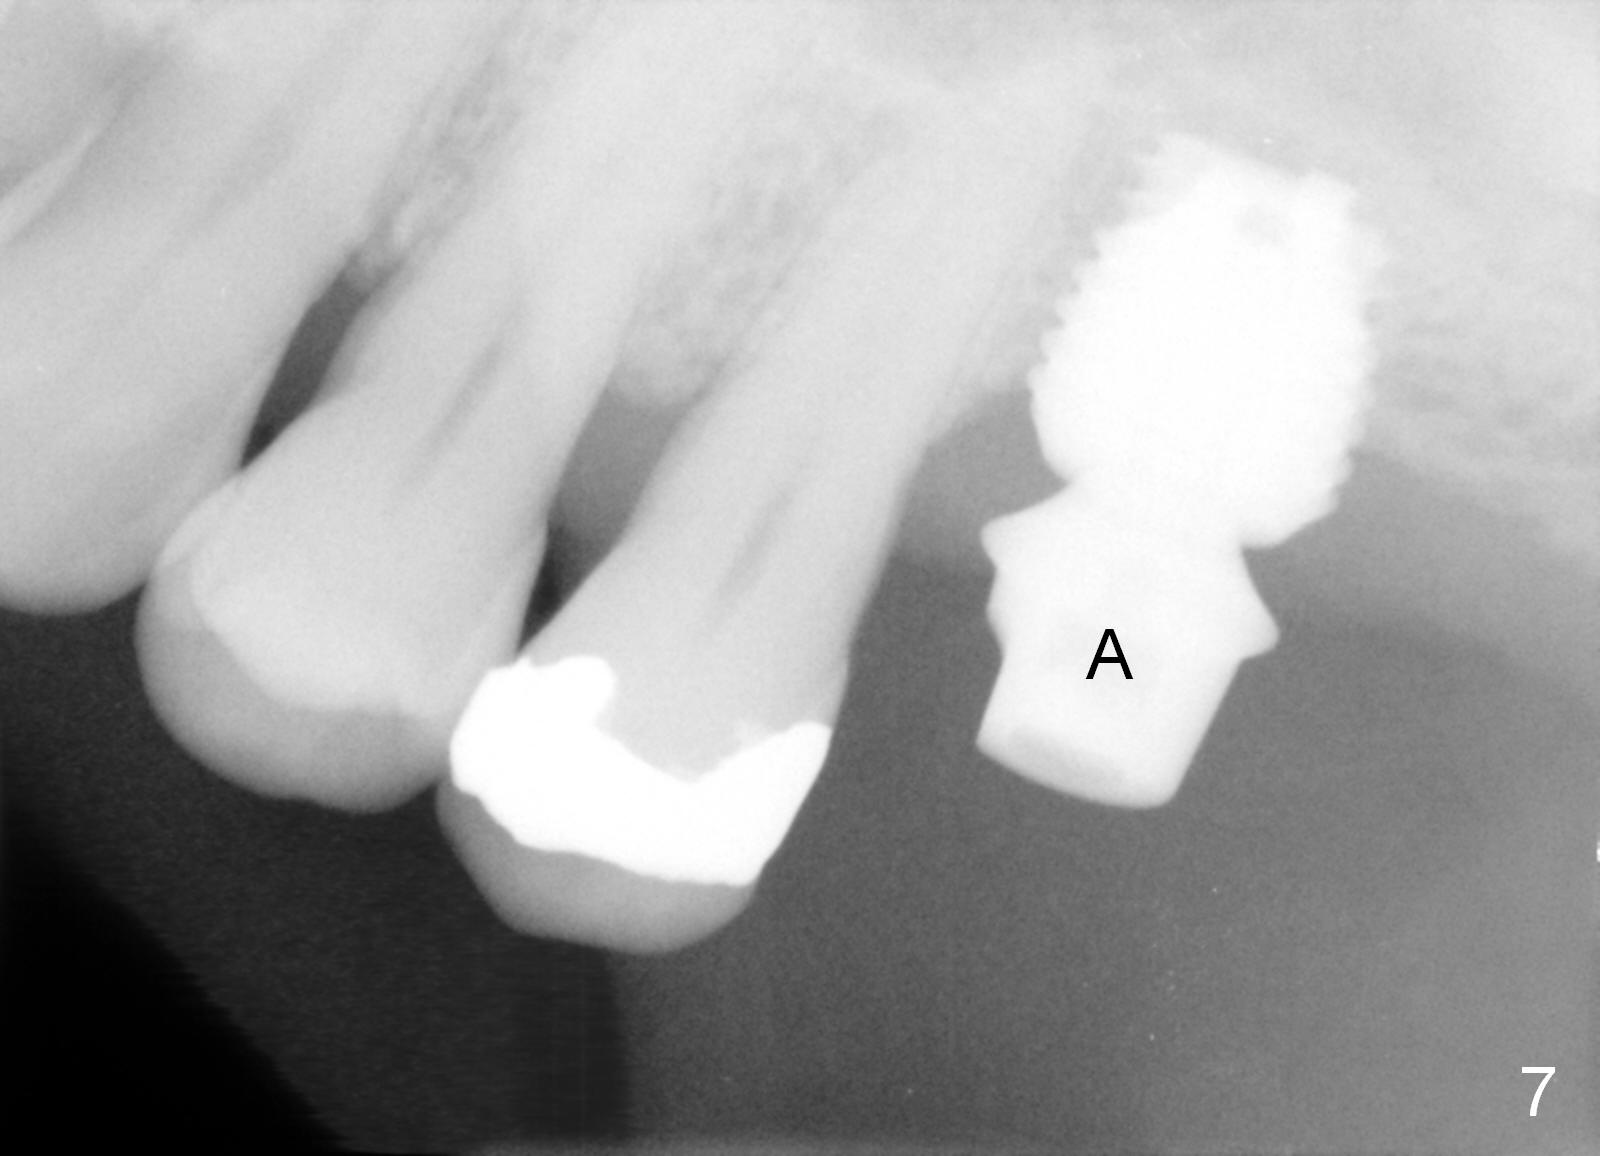

When the patient returns for impression 6.5 months postop, the provisional has dislodged because of the short abutment (Fig.7 A (6.5x4(2) mm). A longer one is placed (6.5x5(3) mm). When he returns for crown cementation 8.5 months postop, the provisional is retentive. The distal implant plateau is still exposed. Post-cementation panoramus shows that the distal 3 threads are not covered by the bone and that the crown/implant ratio is 5:3 (Fig.8). Implants are recommended at #3 and 30 (Fig.9). There is a distinct layer of bone apical to the implant at #14 22 months post cementation (Fig.10 *). In spite of exposure of 2-3 threads distally, there is no sign of peri-implantitis. It appears that the implant is subgingival (Fig.11 (BW) white dashed line: gingival margin). The implant remains infection free 3 years 10 months post cementation (Fig.12) due to the thick gingiva and good oral hygiene.